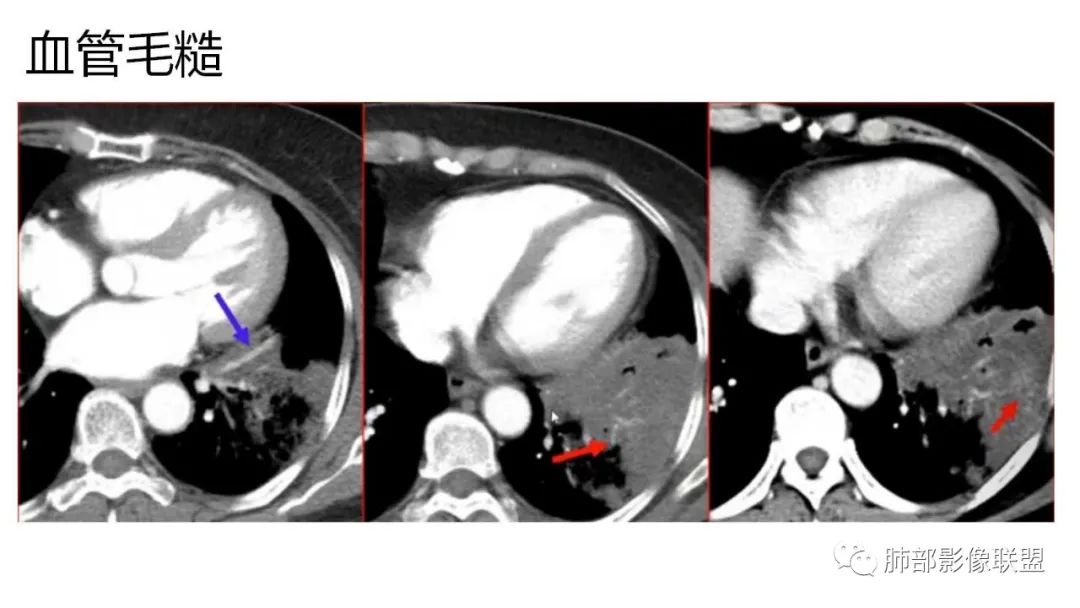

4、增强后不均匀强化,存在低强化区呈弱强化或无强化,因此可见“血管造影征。”血管毛糙与肺炎有统计学差异。